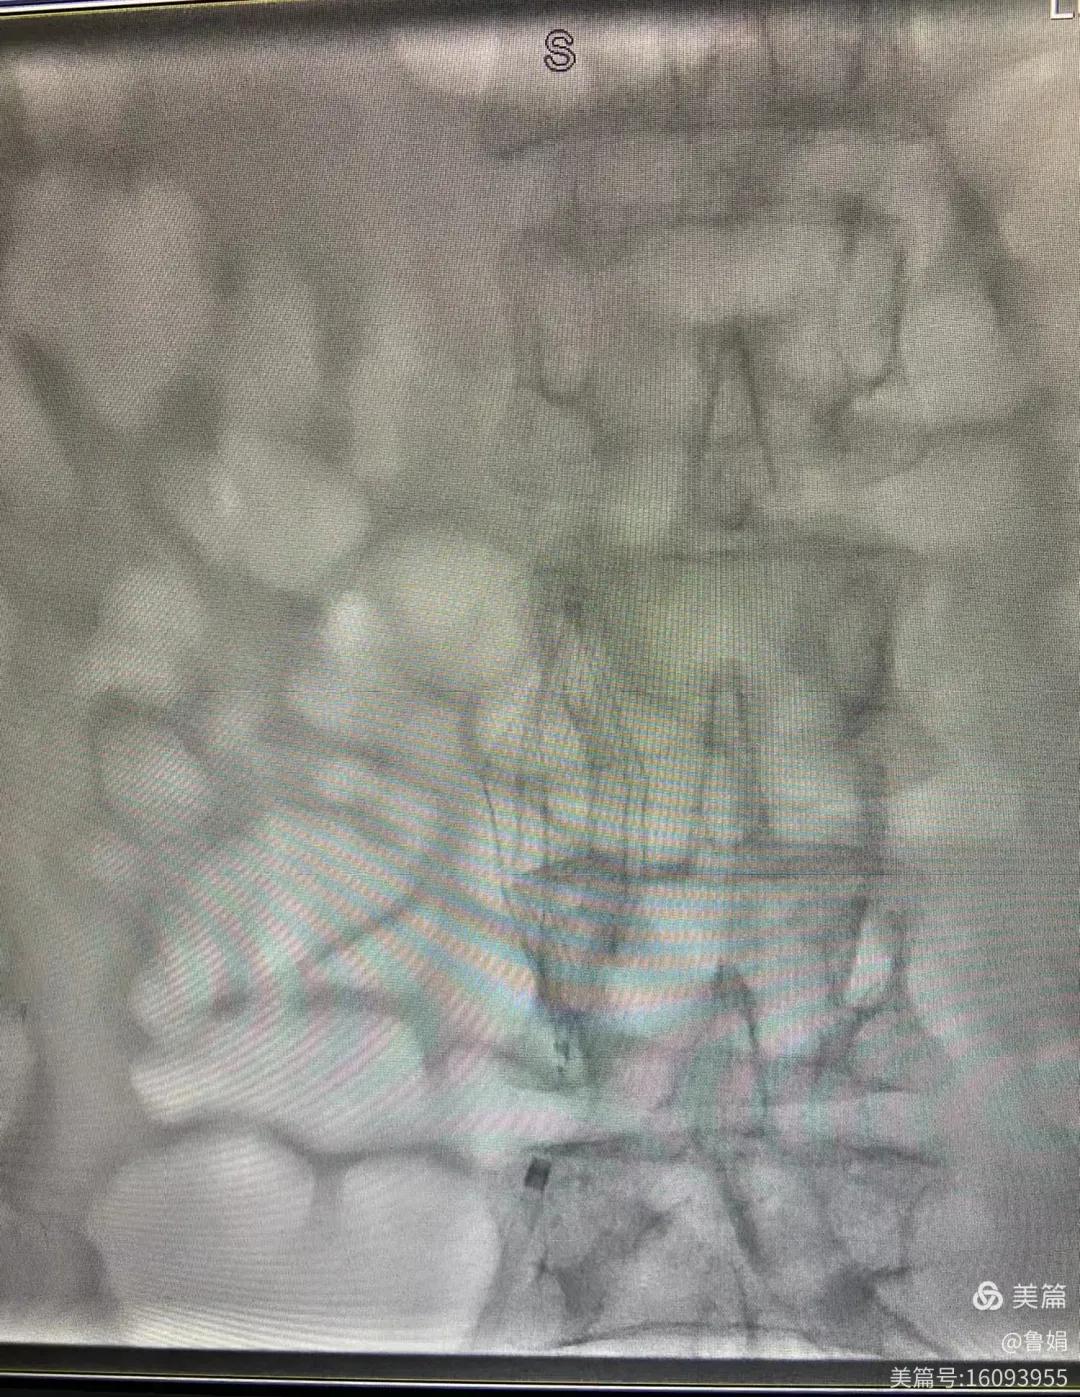

11月3日,漯河市中醫院血管外科副主任周創業與腦二科介入醫生孫亞中,兩位醫生為一位腦梗死伴下肢深靜脈血栓形成患者成功開展下腔靜脈濾器置入術。

圖片術后濾器順利植入

經認真查看患者病例,探討患者病情及術中潛在風險因素,多科會診后急診為患者開展介入手術,術中周創業副主任、孫亞中副主任中醫師二人通力合作,手術順利,病人術中出血少,生命體征平穩,現在腦二科病房繼續對癥治療。(介入中心:魯娟)